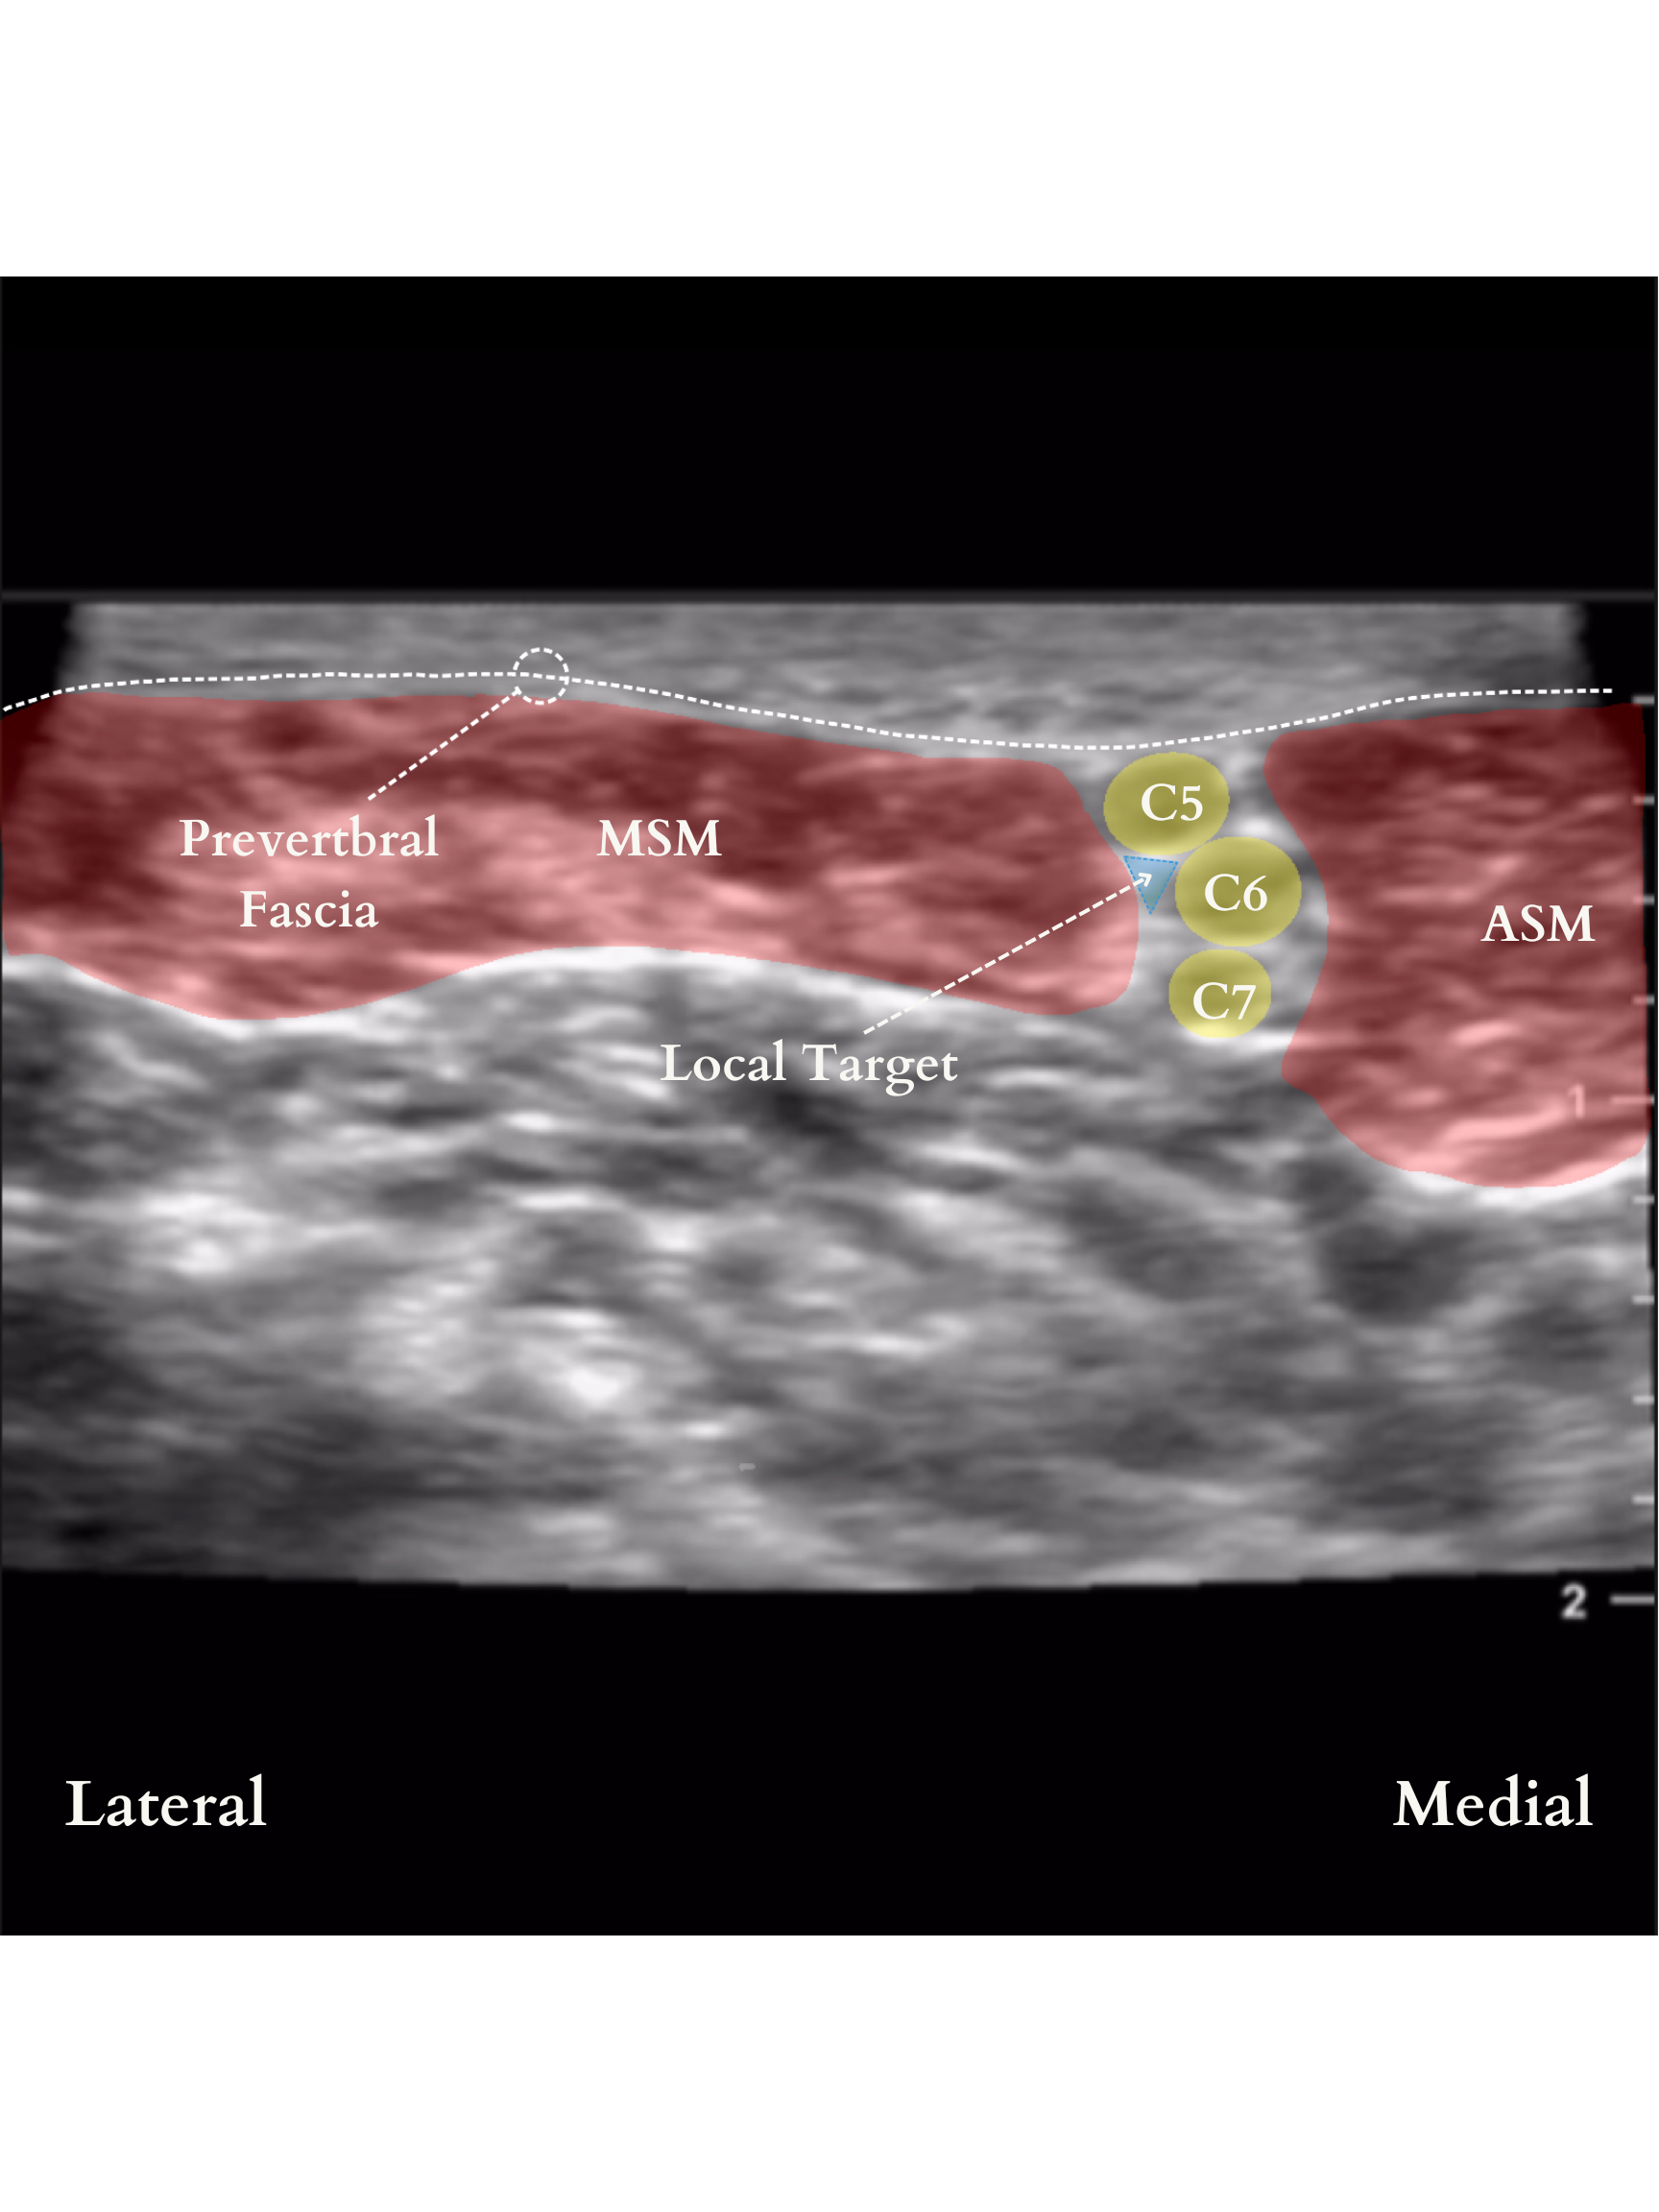

The posterior approach is considered the safest since the major vessels, nerves and sympathetic ganglia are anterior. It is also popular for ease of approach. In the classical approach, the ultrasound probe is placed over the sternocleidomastoid muscle at the level of the cricoid cartilage (transverse process of C6), between the anterior and the middle scalene muscles until the roots of C5, C6, and C7 are identified as three round hypoechoic spheres “traffic light sign”.

A common way to confirm the correct sonoanatomy is to place the probe in the supraclavicular fossa to identify the subclavian artery and the brachial plexus in what is referred to as the “bundle of grapes” sign. The probe is then translated in a cephalad direction keeping the nerves in view until the roots of C5, C6, and C7 are identified between the anterior and middle scalene muscles. A paper by Franco et al suggests that while the “traffic light sign” usually has 3 “lights,” they may in fact be made up of only 2 nerves (C5 and a split C6). The important clinical implication is that “an injection attempted between what is commonly perceived as the gap between C6 and C7 would indeed be an intraneural injection at C6, which could potentially spread toward the neuraxial space.”

As such, needle insertion is in plane targeting the pre-fascial space near the C5 and C6 nerve roots.

Another common way to identify the Brachial Plexus at the level of the Interscalene Groove is to trace the anterior rami of individual cranial nerves. As mentioned above, this may help identify instances where the three visible nerve roots are actually C5 and a split C6 (as captured in the video below!)